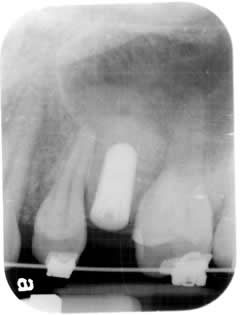

Orthodontic / Implant:

Braces is used in this case first to create sufficient space in order to place a single tooth implant.